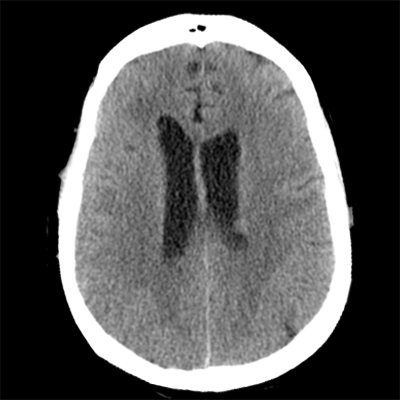

You arrive at the patient's room. You quickly examine her. Her left pupil is truly dilated and unreactive. Her right pupil is also dilated and unreactive, and also deviates to the right. She is unable to follow commands but is moving her extremities spontaneously. The right side of her body seems to be moving slightly less than her left. You escort the patient with RRT and your neurology colleague to radiology, where a non-contrast head CT and CTA head/neck are obtained.

HCT part 1 HCT part 2 HCT part 3

The non-contrast head CT looks generally similar to her prior scan. There's no new hemorrhage anywhere. There's no mass effect causing midbrain compression. The vessel imaging also looks unrevealing-- a slightly hypoplastic right A1 segment, but no clear LVO in either the anterior or posterior circulation. There's no vasoconstriction.